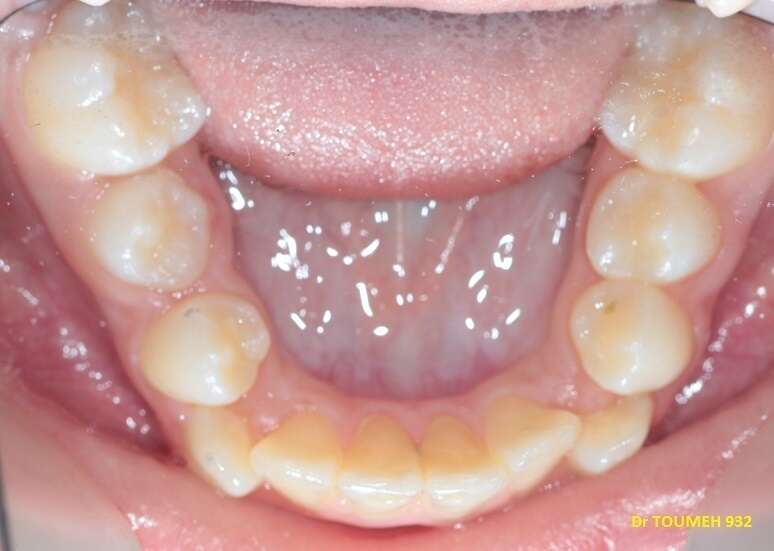

Avant

Après